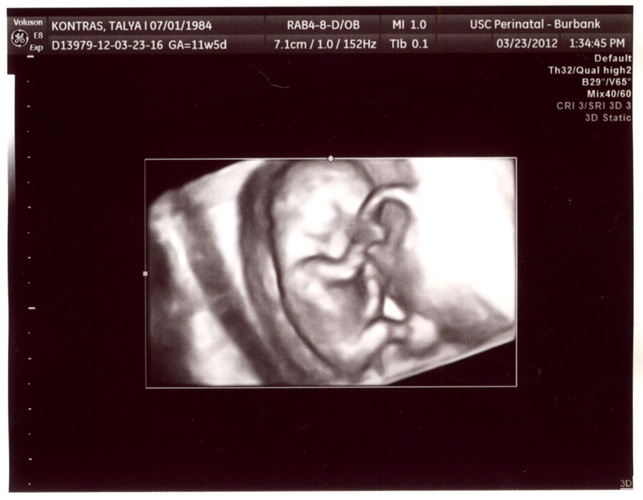

3:41 PM, Friday, March 23rd, 2012:

I just promised everyone I wouldn't be that dad. LOL. Swear to you that if I wasn't so unbelievably blown away by these 10 minutes, I wouldn't be doing an entry... but, WOW:

I didn't even bother with making a professional video out of that. That is the straight up file from the camera. What an unbelievable 10 minutes. That little bugger is movin' all over the place! It's only 11 weeks! And yes, although only 95% sure, the doctor thinks it's a girl. We'll save the name until we know for sure. Looks like that will be April 9th... which is still way early from what I've read, but hey - I just watched a 3D image of my baby on an HDTV and posted it across the world today on these magical tubes and my parents can watch it on their FUCKING PHONES. Everything I've ever understood about life has just been blown out of the world. Do you mind if I take 10 minutes and watch that entire thing over again?

First, how cool is it that you can see the mouth and a smile there. :) But, you're tellin' me that's the clitoris? Uhm. If the girl has a clitoris down to her thigh, what does that make her? And how stupid am I for typing that sentence about my own daughter? (sigh). I'll take the doctor's word for it about the direction being the tell-tale sign, but since she's right at 11 weeks measurement-wise, I am baffled that you can have an even 90% assurance. Everything I read said 16 weeks... and 13 at the earliest. He did admit before 12 weeks he's more guarded and has been wrong. In fact his best friend did an ultrasound the same time, it looked just like this, he told them it was a girl and a few weeks later he went "nope, it's a boy". Again, I want a boy and a girl so this just means the girl is first. :)

Now, this 3D stuff? What?

It's nowhere near as cool as the video though. I had NO idea you could do that at 11 weeks. When he popped that on my jaw dropped to my knees. Talya is barely showing. We still can't even believe it. And the 4D Realtime thing? What the how? WOW. I mean, WOW. Again, I do NOT want this blog to be every moment the kid does anything different, and I don't want to load an hour's worth of ultrasounds on YouTube every couple of months, but I am legitimately shocked at how far technology has come with SOUNDWAVES. You know? Supremely awesome. So excited. So happy. Cannot believe I ever for one second was sad about anything else on the planet because life is so wonderful oh my GOD holy balls.